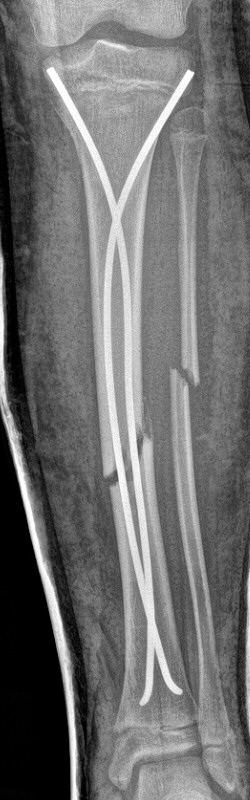

Tibia och fibula-frakturer, tibia spikats med 2 TEN-spik, sista 2 bilderna efter 5 veckor, då inte alls ömmande över frakturerna.